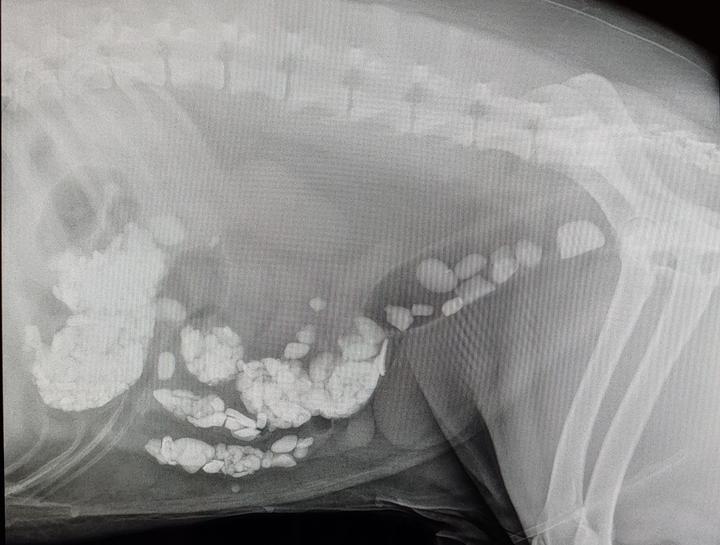

Pet Digital Radiology

Digital x-rays assist in diagnosing illness & injury.